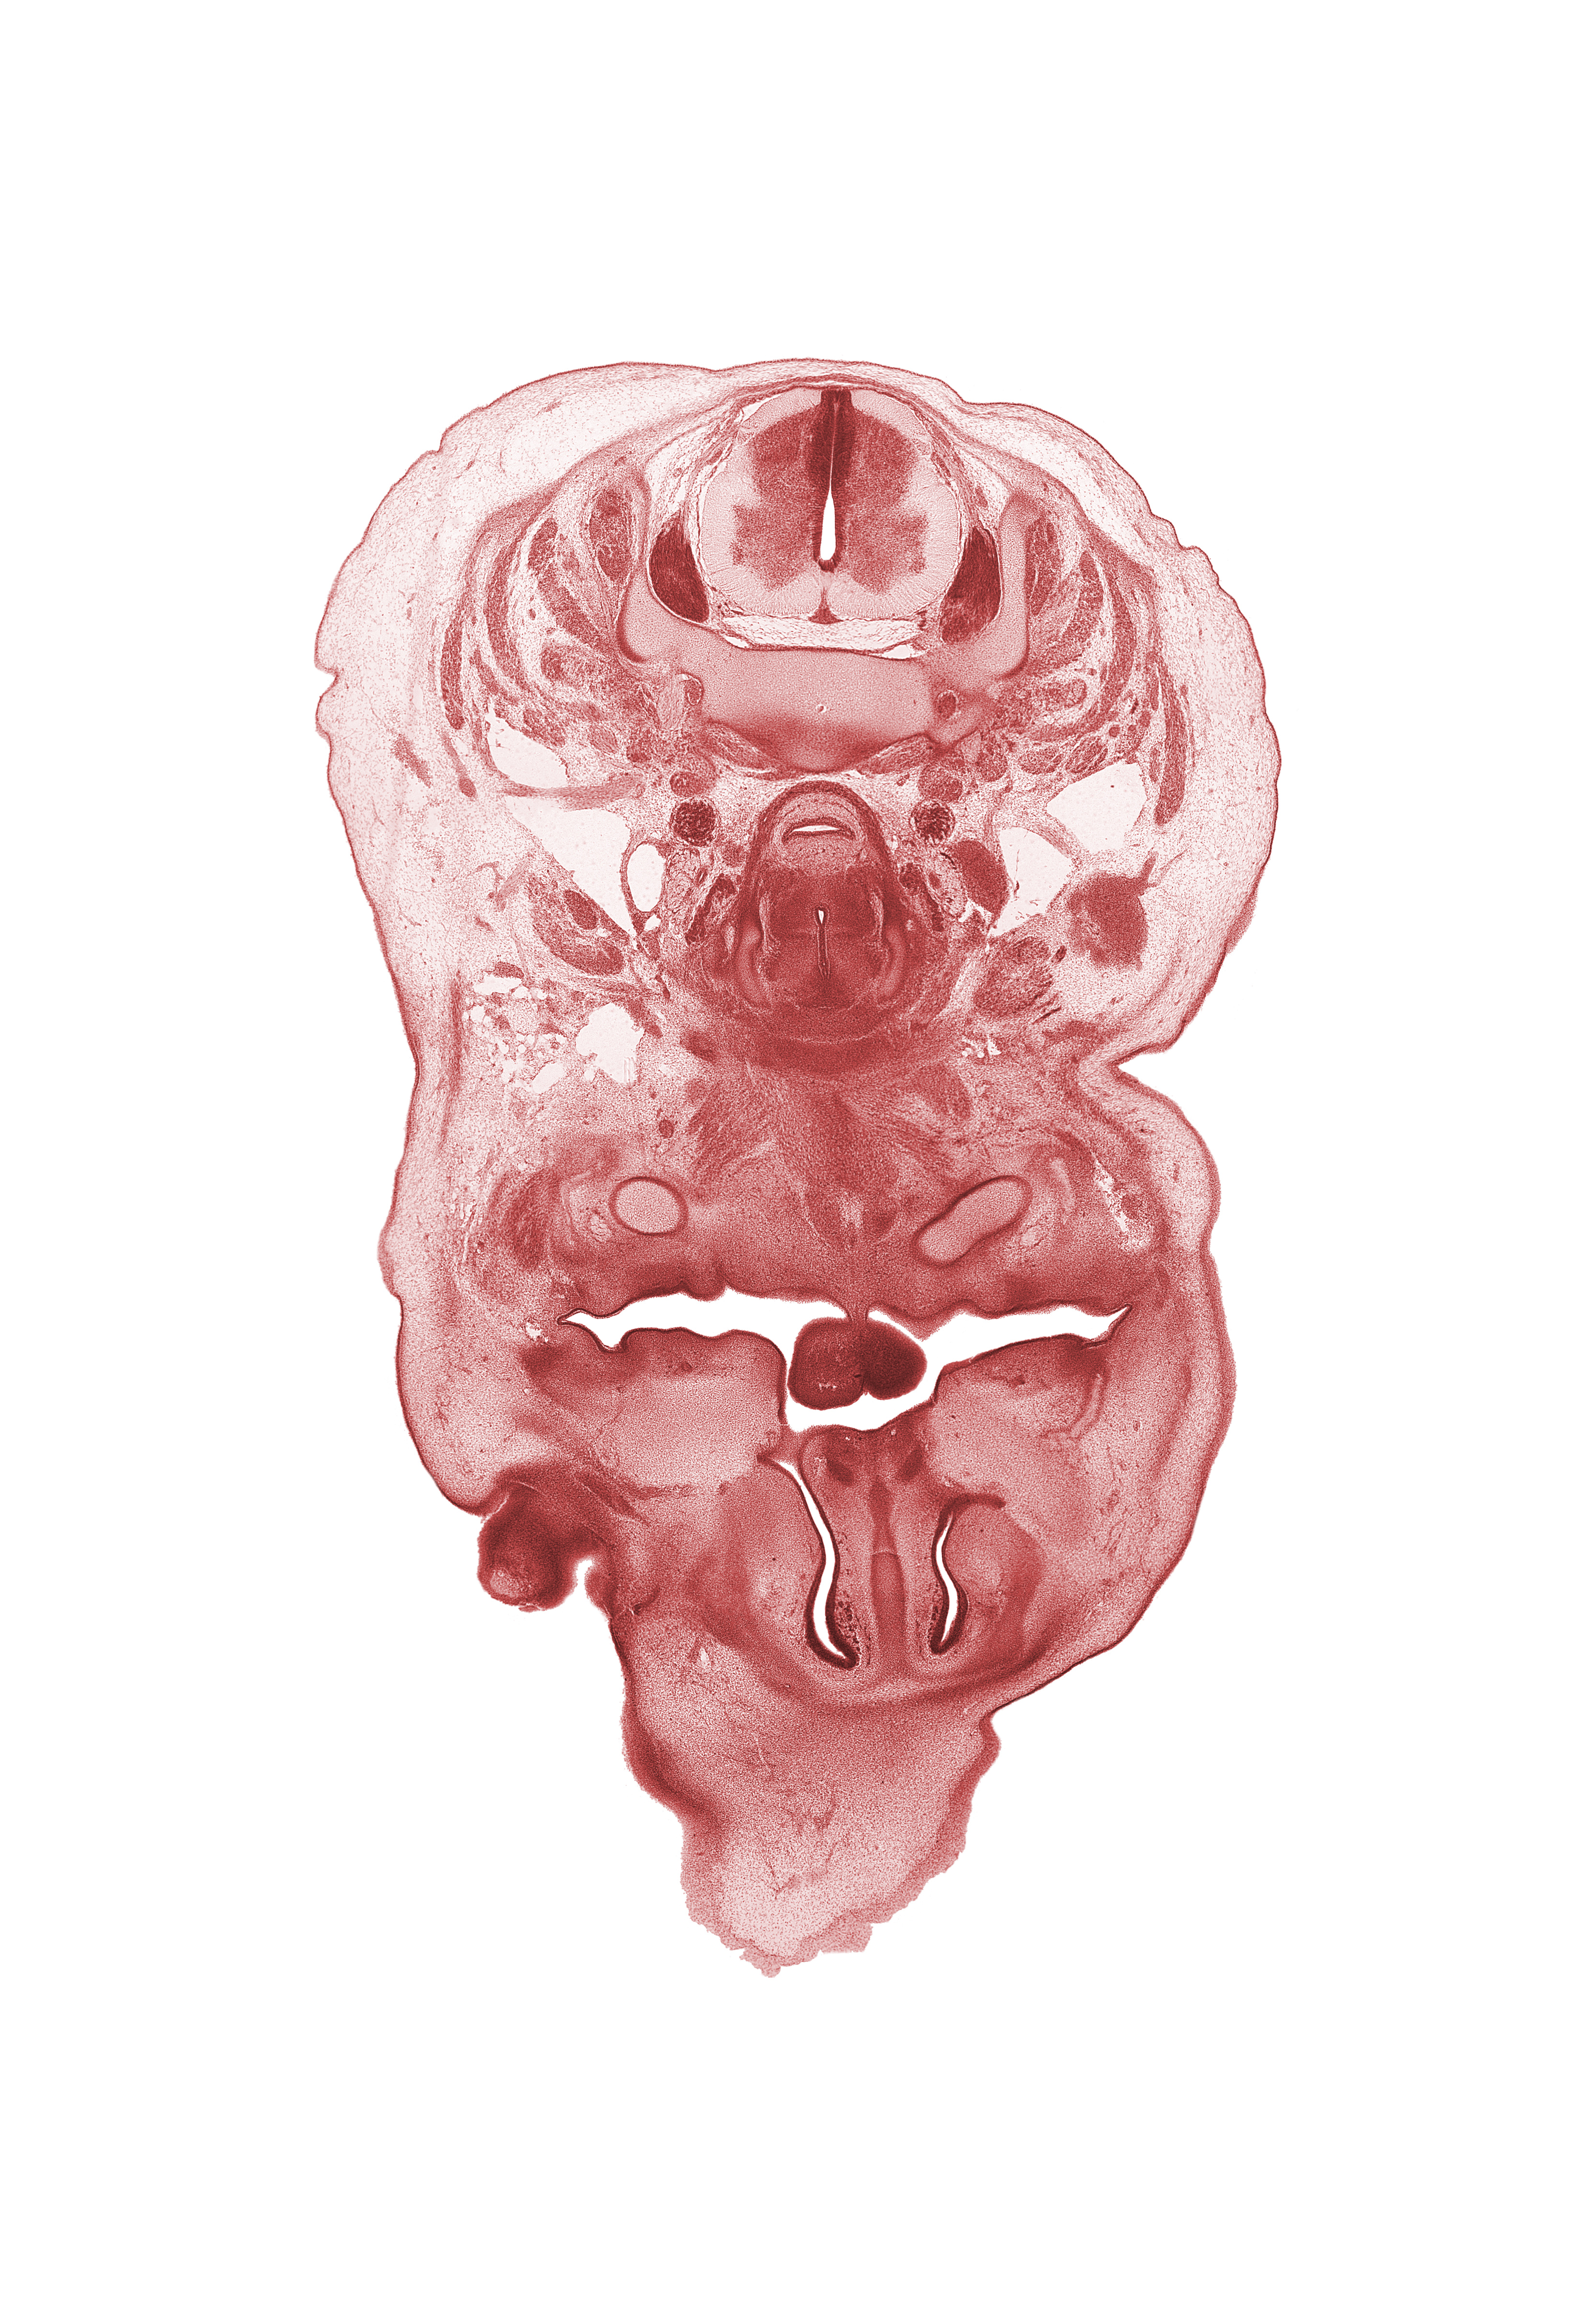

Carnegie Embryo #462 | Location: 6-01-05

Keywords: C-5 spinal ganglion, anterior spinal artery, caudal edge of eyeball, external jugular vein, frenulum of tongue, internal carotid artery, interorbital ligament, jugular lymph sac, laryngeal condensation, longus cervicis muscle, nasal capsule, nasal cavity (nasal sac), nasal septal cartilage, oral cavity, pharyngeal arch 1 cartilage (Meckel), platysma muscle, semispinalis capitis muscle, semispinalis cervicis muscle, splenius muscle, sternocleidomastoid muscle, subarachnoid space, superior parathyroid gland, trapezius muscle

Source: The Virtual Human Embryo.